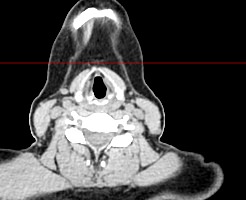

Оптимальным методом обследования гортани и голосовых связок является мультиспиральная компьютерная томография. Метод позволяет подробно визуализировать состояние данной анатомической области и выявить патологические изменения, которые незаметны при ларингоскопии (визуальный осмотр гортани с помощью специальных инструментов), проведении УЗИ и обычной рентгенографии.

Компьютерная томография особенно полезна для оценки состояния хрящей гортани, которые лучше всего визуализируются с помощью данного исследования. В частности, мультиспиральная КТ позволяет выявить распространение рака гортани в ткань щитовидного хряща и другие окружающие структуры.

В клинике «Доступная медицина» исследование выполняется на современном 128-срезовом мультиспиральном компьютерном томографе экспертного уровня TOSHIBA AQUILION CXL, который послойно сканирует исследуемую область с толщиной среза от 0,5 мм.

На полученных снимках можно оценить состояние всех структурных элементов гортани, голосовых складок, хрящей, а также лимфатических узлов, сосудов и шейных позвонков на исследуемом уровне. Инновационные возможности аппарата позволяют построить 3D-модель зоны исследования, которая дает наглядную картину пространственного расположения органов, что бывает особенно важно при планировании хирургических операций.